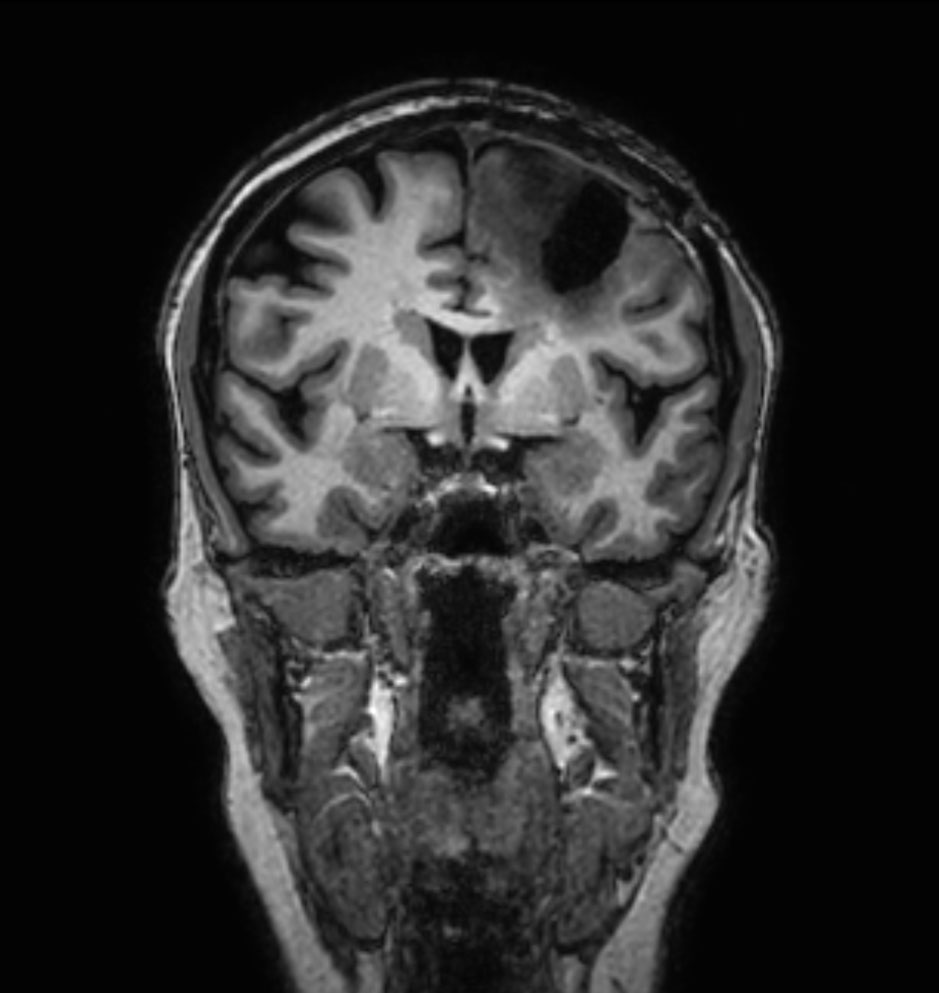

3D FLAIR - Coronal reformat